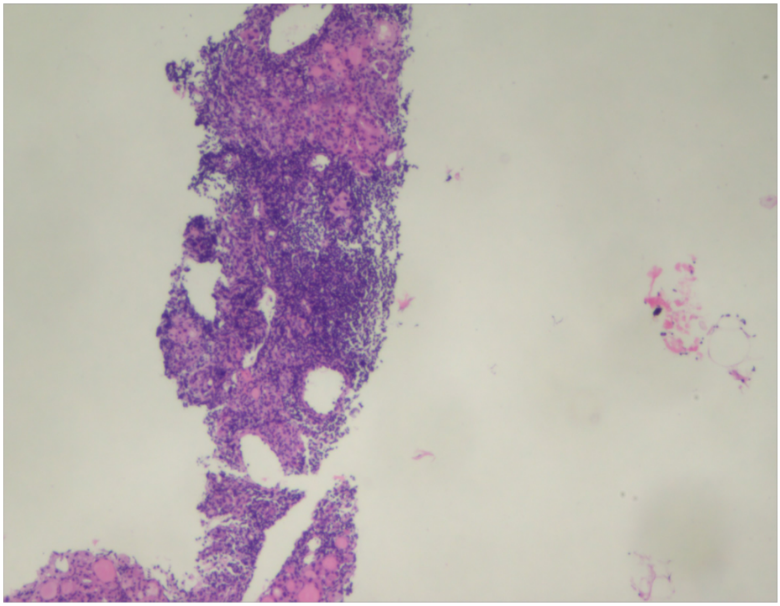

超声引导下行粗针穿刺病理,镜下见间质部分区纤维组织增生,部分区见大量淋巴细胞浸润,部分区呈慢性肉芽肿性炎改变,部分区域见少量钙化。

病理结果提示肉芽肿性甲状腺炎(图 9 )。

图 9 病理结果提示肉芽肿性甲状腺炎